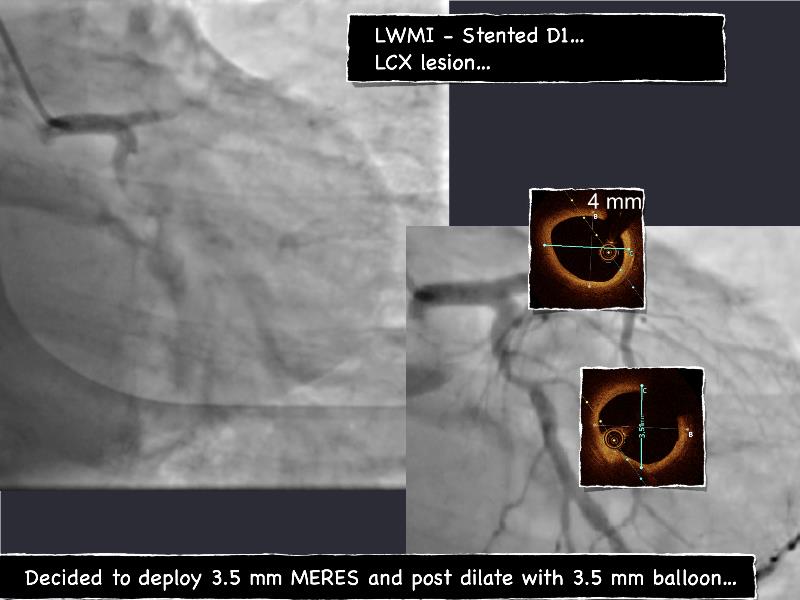

- To understand novel tools and techniques for effective management of bifurcation lesions and long diffused lesions using dedicated stenting solutions